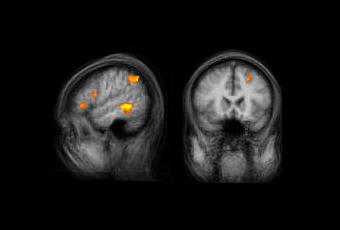

Si trabajas cerca de un programador sin duda te habrás preguntado, como yo, qué es exactamente lo que sucede dentro de su cabeza. Se trata de criaturas muy particulares – que no se me enfaden – capaces de concentrarse en la tarea de crear código como si acamparan en el corazón de Matrix. Pues bien, lo que ves sobre estas líneas es la imagen de resonancia magnética del cerebro de un programador - el primer estudio de este tipo que se realiza – y las áreas iluminadas son las zonas que se activan mientras lee código.

Para averiguarlo, un equipo de investigadores internacional, dirigido por Janet Siegmund, de la Universidad de Passau, ha elaborado un primer estudio en el que sometieron a 17 estudiantes de informática (todos con conocimientos de programación y solo dos de ellos chicas) a una prueba con resonancia magnética funcional. En el experimento, tumbaron a los sujetos en el escáner y monitorizaron su actividad cerebral mientras leían unas líneas de código. Estas líneas de código indicaban una tarea de impresión del ordenador y los participantes debían predecir, en un tiempo determinado, qué texto imprimiría la máquina.

El resultado, por sorprendente que parezca a muchos, fue que las áreas cerebrales que se activaron tienen en principio más relación con el lenguaje que con el mero cálculo matemático. “No hay una prueba clara de que aprender lenguaje de programación sea como aprender una lengua extranjera”, asegura Christian Kästner, coautor del estudio, “pero nuestros resultados muestran que hay similitudes claras en la activación cerebral que indican que la hipótesis es plausible”.